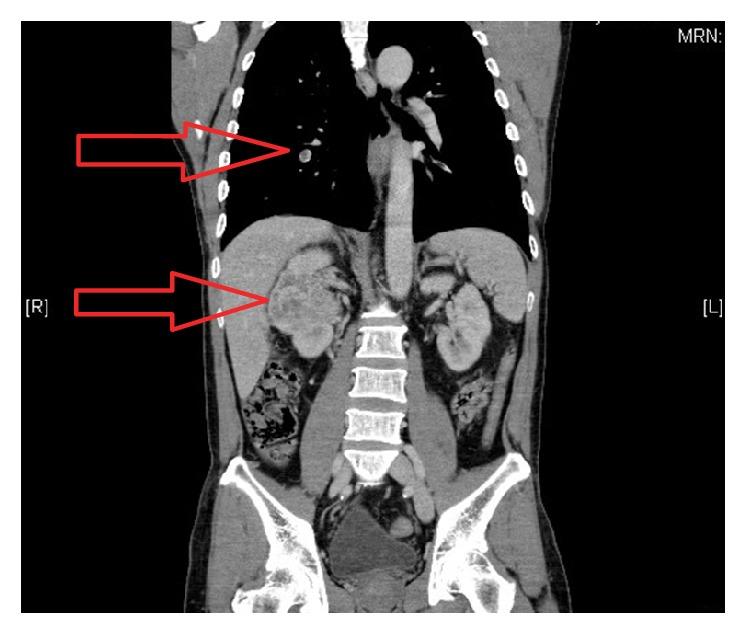

We report a rare case of advanced metastatic renal cell carcinoma which initially presented to the clinic with back and forehead lumps. Ultrasound imaging of the lumps and later of the abdomen picked up a right renal tumour which led to further computed tomography and bone scans. The bone scan confirmed that the forehead lump was a calvarial metastasis and such a presentation for metastatic RCC is very rare which bears a significantly poorer prognosis.

我们报告了一例罕见的晚期转移性肾细胞癌病例,该患者最初因背部和前额肿块就诊。对肿块以及随后对腹部进行的超声检查发现了右肾肿瘤,进而进行了进一步的计算机断层扫描和骨扫描。骨扫描证实前额肿块为颅骨转移,转移性肾细胞癌出现这种表现非常罕见,且预后明显较差。